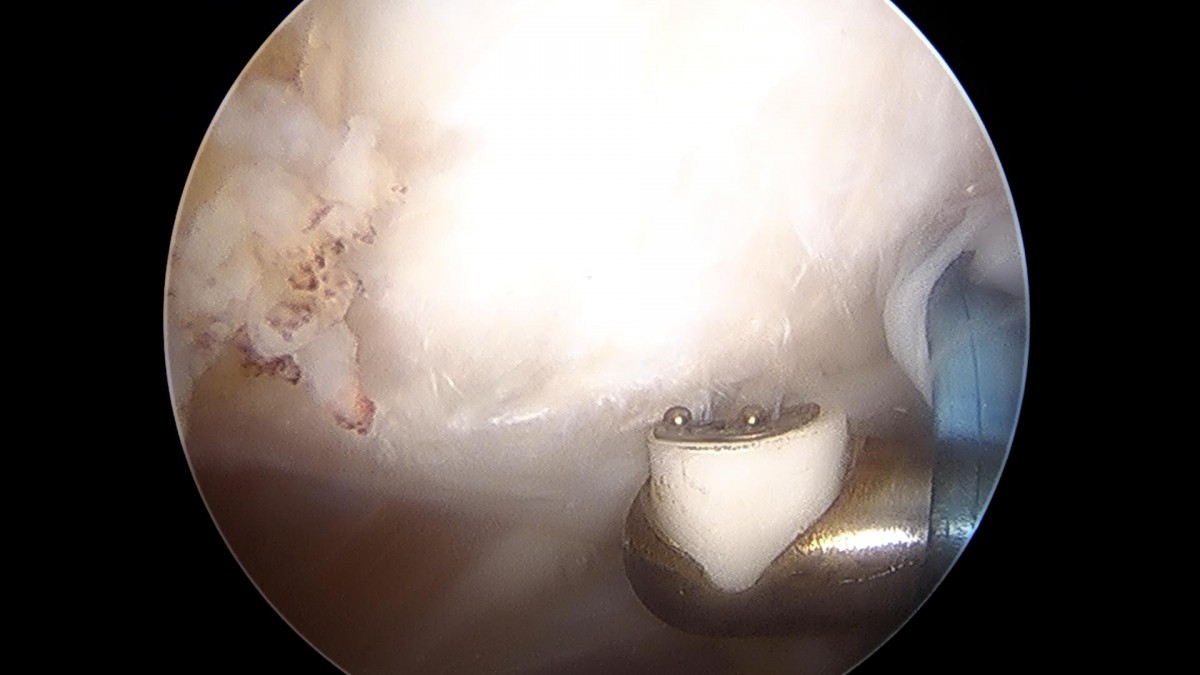

이재상원장님 어깨 회전근개 봉합술 (1094)이현O 환자

작성자 최고관리자 댓글 0건 조회 1,224회 작성일 22-02-23 14:11